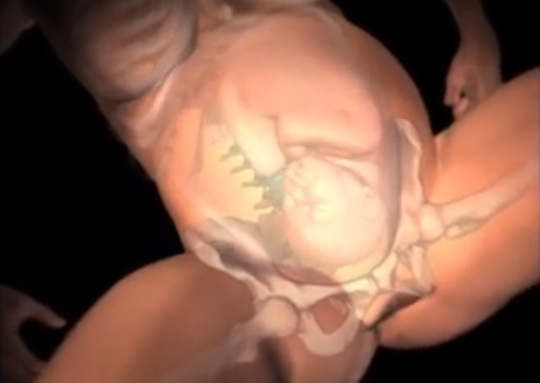

Un detallado y gráfico clip de la página de Facebook “Videos de Embarazo” se volvió viral. No es menor, ya que la corta animación retrata cómo el cuerpo de la mujer se adapta a la hora de dar a luz, además del increíble y difícil viaje que comienza el bebé en el canal del parto.

El video muestra el proceso completo del parto vaginal y deja a todas las madres del mundo como unas campeonas, ya que lo que soportan es sólo para valientes. Todo comienza con el bebé dado vuelta en el útero y claramente, quedándose sin espacio.

Luego, la animación muestra cómo la cervix se va dilatando -a veces durante horas, otras veces demasiado rápido- hasta alcanzar los 10 centímetros, lo cual sigue sin parecer como mucho espacio para que quepa un bebé.

Aún así, el retoño desciende por el canal del parto, mientras el cuerpo de su madre se estrecha para acomodarlo suavemente hasta la salida.

Apenas sale su cabeza, el bebé gira sus hombros a través de la vagina, para así poder salir hacia el mundo. Y su agotada madre al fin podrá tomarlo en brazos, tras 9 largos meses de espera. Te invitamos a verlo por completo a continuación: